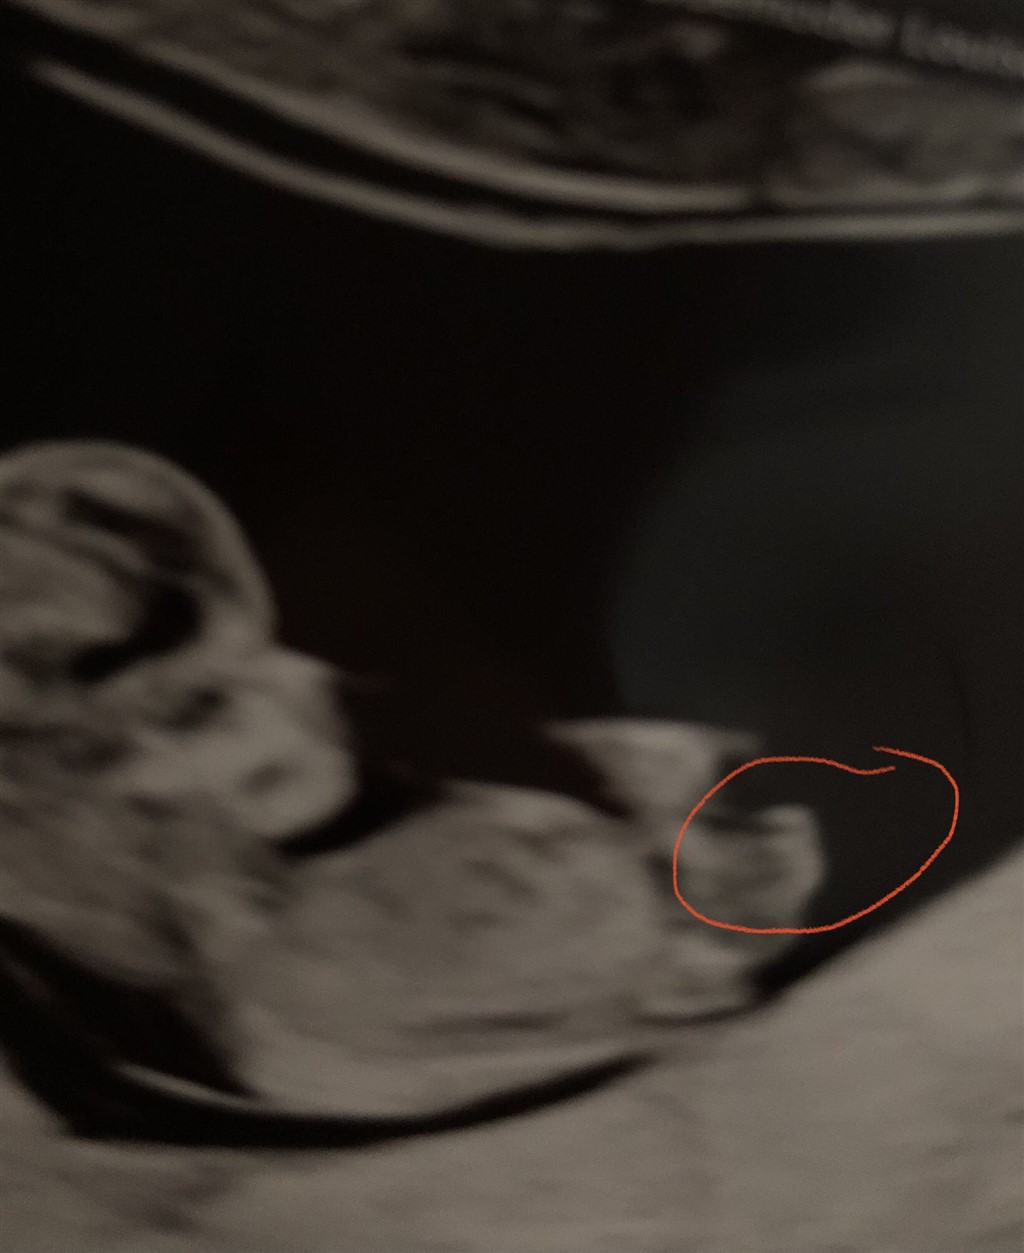

Jeg er overbevist om, at det er en dreng, men det er taget 11+5, så en anelse tidligt.

Tænker I det kan vise sig at være en pige?

Baby ligger en ikke helt lige, men er drejet. Det kan godt være, at det derfor er lidt sværere at få et retvisende billede